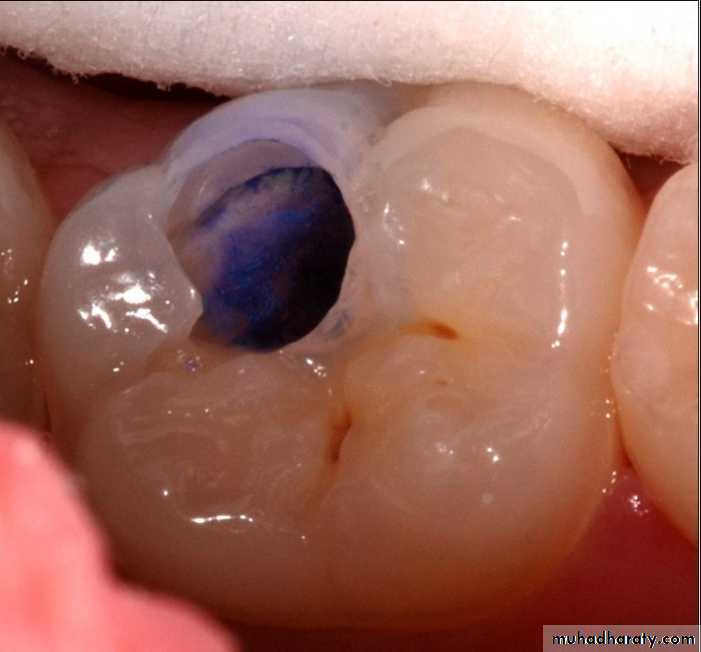

Dye penetration method

Use of basic fuschin in propylene glycol for the diagnosis and treatment of carious dentin has been given by Fusayama, 1980. The dye was found to be carcinogenic.To overcome this disadvantage, acid red or methylene blue were used, but methylene blue is slightly toxic.